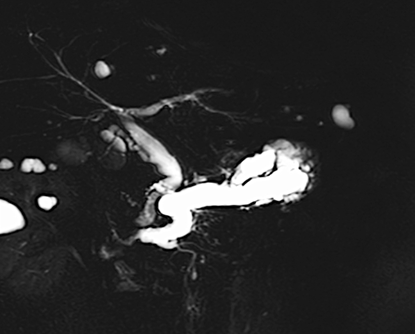

本症例では化学療法中に黄疸が出現しました。MRCP検査では、胆管の左枝、前区域枝、後区域枝のそれぞれに狭窄を認めました。

ERCPを行ったところ、同様にこれらの胆管に狭窄を認めたため、それぞれの胆管に対して胆汁の流れを確保する必要がありました。そのため、3本のプラスチックステントを留置しました。

ステント留置後、黄疸は速やかに改善し、その後化学療法を再開することができました。